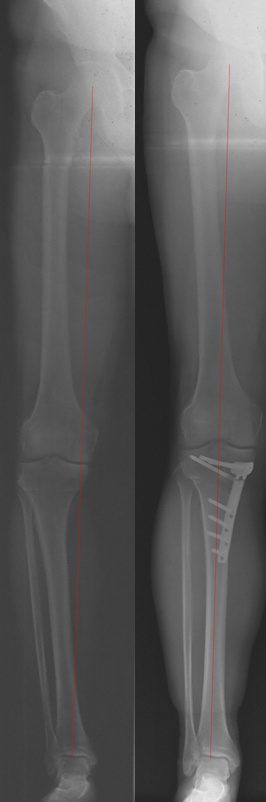

O- bzw. X-Beine sowie Torsionsabweichungen

Im Erwachsenenalter sind ebenfalls nicht selten Achsabweichungen festzustellen, welche mehr oder weniger ausgeprägte Beschwerden verursachen können. So führt eine Achsabweichung der Beine zu einer ungleichen Lastverteilung unter anderem im Bereich des Kniegelenkes, was die Überlastung eines Gelenkabschnittes mit erhöhtem Knorpelverschleiß und somit eine vorzeitige Arthrose mit Schmerzen zur Folge haben kann. Auch bei Erwachsenen mit bereits eingetretener Arthrose sind konservative bzw. auch operative Behandlungsmöglichkeiten gegeben, über die wir Sie gerne informieren und einen Behandlungsplan mit Ihnen entwickeln.

Beispiel eines operierten Patienten mit einseitiger Kniegelenksarthrose bei O-Bein: Röntgenbild vor- und nach Operation